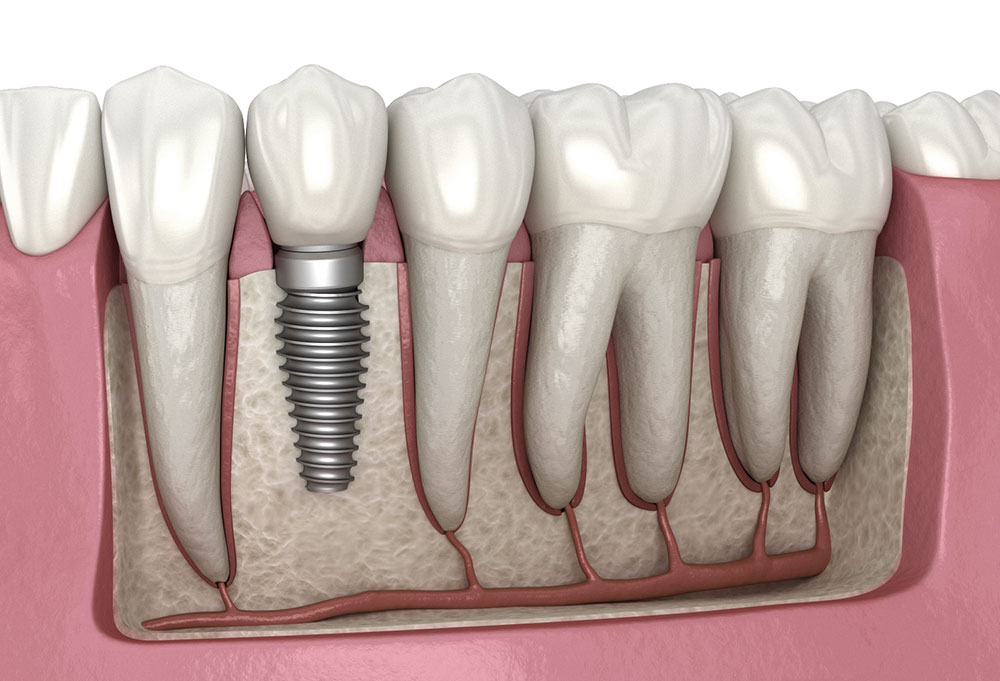

Diş implantı, eksik dişlerin yerine çene kemiğine yerleştirilen titanyum yapay köklerdir. MeyDental Antalya’da uygulanan implant tedavisi, doğal diş görünümü ve güçlü çiğneme performansı sunar. Kalıcı, estetik ve güvenilir bir çözüm arayanlar için en ideal yöntemdir.

Diş implantı, eksik dişlerin yerine kalıcı ve doğal bir çözüm sunan modern bir tedavi yöntemidir. Çene kemiğine yerleştirilen titanyum yapay kökler, hem estetik hem de fonksiyon açısından gerçek dişlerle aynı hissi verir. MeyDental Antalya’da implant tedavileri, ileri teknoloji, uzman hekim kadrosu ve yüksek başarı oranı ile uygulanmaktadır.

MeyDental’de implant süreci kişiye özel olarak planlanır. Muayene sırasında çene yapısı, kemik yoğunluğu ve hastanın genel ağız sağlığı detaylı şekilde değerlendirilir. Gerekli durumlarda kemik grefti gibi ek işlemlerle implant için ideal ortam hazırlanır. Yerleştirilen implantlar, kemikle bütünleştikten sonra üzerine estetik ve dayanıklı porselen ya da zirkonyum dişler yerleştirilir.